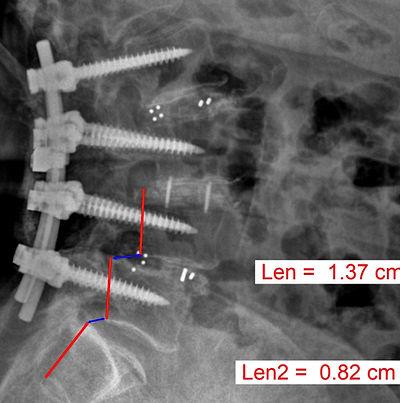

According to the American Society of Anesthesiologist Failed Back Surgery Syndrome

1st Spinal Surgery Success Rate: 45%

55% Fail Rate

2nd Spinal Surgery Success Rate: 30%

70% Fail Rate

3rd Spinal Surgery Success Rate: 15%

85% Fail Rate